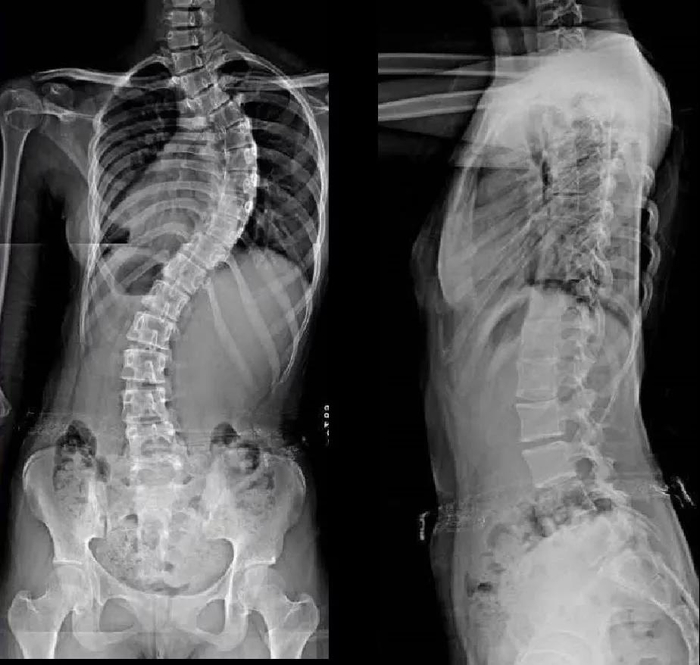

脊柱侧弯是脊柱的三维畸形,冠状面侧方弯曲,水平面轴向旋转,矢状面生理弯曲,前凸或后凸异常。而超过80%的脊柱侧弯是原因不明的,好发于青少年特发性脊柱侧弯,其中又以女性最为多见。

脊柱矢状面上胸椎后凸,冠状面上s型弯曲,腰椎前凸曲度减少,椎体和骨盆旋转